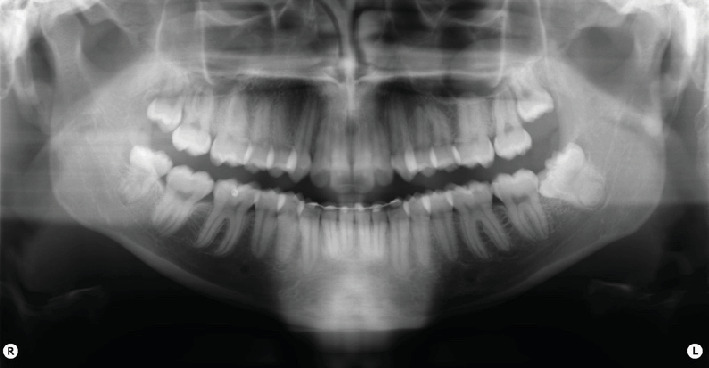

Introduction: Gemination and fusion are rare developmental anomalies that can present significant diagnostic challenges. Due to the complexity of distinguishing between these conditions, the term "double tooth" is commonly employed in clinical practice. The precise etiology of these anomalies remains uncertain, and their occurrence in permanent dentition-particularly involving molars-is exceptionally rare. This report describes an uncommon case of gemination affecting the mandibular left third molar (tooth 3.8) and provides a comprehensive discussion contextualized within existing literature. The case report was prepared following the CARE guidelines to ensure methodological rigor and completeness. Methods: After an intraoral examination and radiographic assessment-including orthopantomography, periapical radiographs, and cone beam computed tomography (CBCT)-the patient underwent surgical extraction. The procedure involved administering a truncal nerve block to anesthetize the inferior alveolar and lingual nerves, supplemented by local infiltration anesthesia of the buccal nerve. A full-thickness mucoperiosteal flap was elevated, followed by ostectomy and odontotomy to facilitate extraction. The tooth was subsequently removed using a combination of elevators and forceps. Results: Postoperative evaluations conducted at 1.5 and 3 months confirmed complete healing of the surgical site. A detailed analysis of pre- and postoperative radiographic and clinical findings validated the diagnosis of gemination, characterized by coronal continuity with a single root and root canal. Conclusions: Gemination of third molars is exceedingly rare, with only a few cases documented in the literature. To the best of our knowledge, this is the first reported instance of gemination involving the mandibular left third molar (tooth 3.8). This report contributes to the growing body of knowledge on developmental dental anomalies and highlights the importance of thorough differential diagnosis in similar clinical scenarios.

Abstract Image